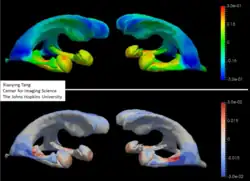

The study of sub-cortical neuroanatomy has been the focus of many studies. Since the original publications by Csernansky and colleagues of hippocampal change in Schizophrenia,[14][15][16][17] Alzheimer's disease,[18][19][20] and Depression,[21][22] many neuroanatomical shape statistical studies have now been completed using templates built from all of the subcortical structures for depression,[23] Alzheimer's,[11][12][24][25][26][27] Bipolar disorder, ADHD,[28] autism,[29] and Huntington's Disease.[30][31] Templates were generated using Bayesian template estimation data back to Ma, Younes and Miller.[32]

Shown in the accompanying Figure is an example of subcortical structure templates generated from T1-weighted magnetic resonance imagery by Tang et al.[11][12][13] for the study of Alzheimer's disease in the ADNI population of subjects.